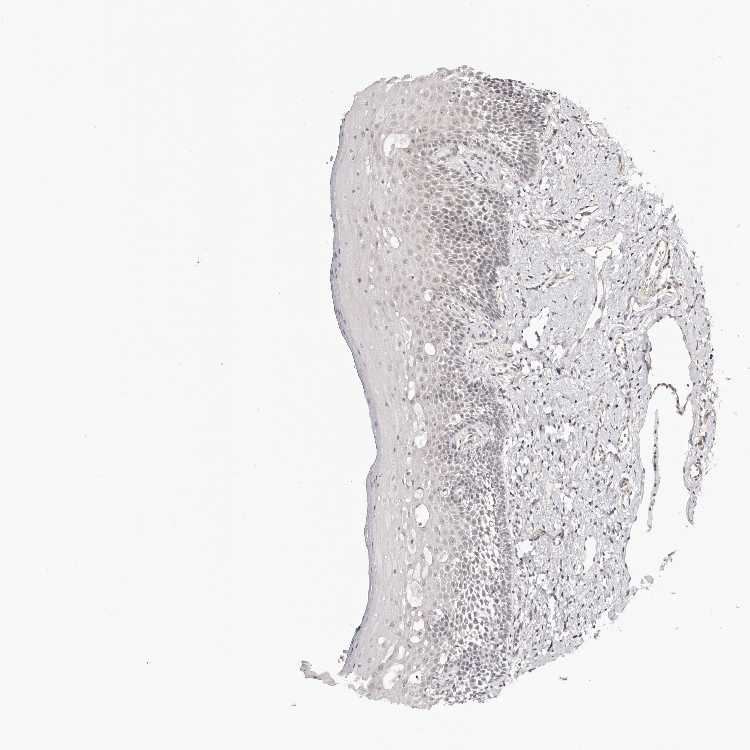

NOL12